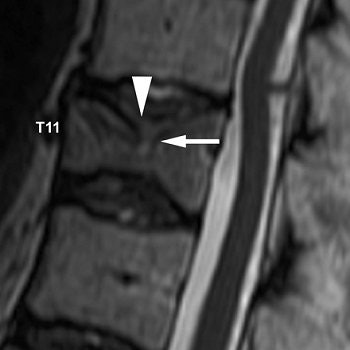

| A 68-year-old woman with history of long-term steroid use for chronic obstructive lung disease. Sagittal T2-weighted image before vertebroplasty shows compression fracture of T11 vertebral body with concave deformity. Cortical defect is noted in superior endplate (arrow). Hyperintensity is noted in adjacent desiccated intervertebral disks, which is more prominent at T10-T11 (arrowhead). |